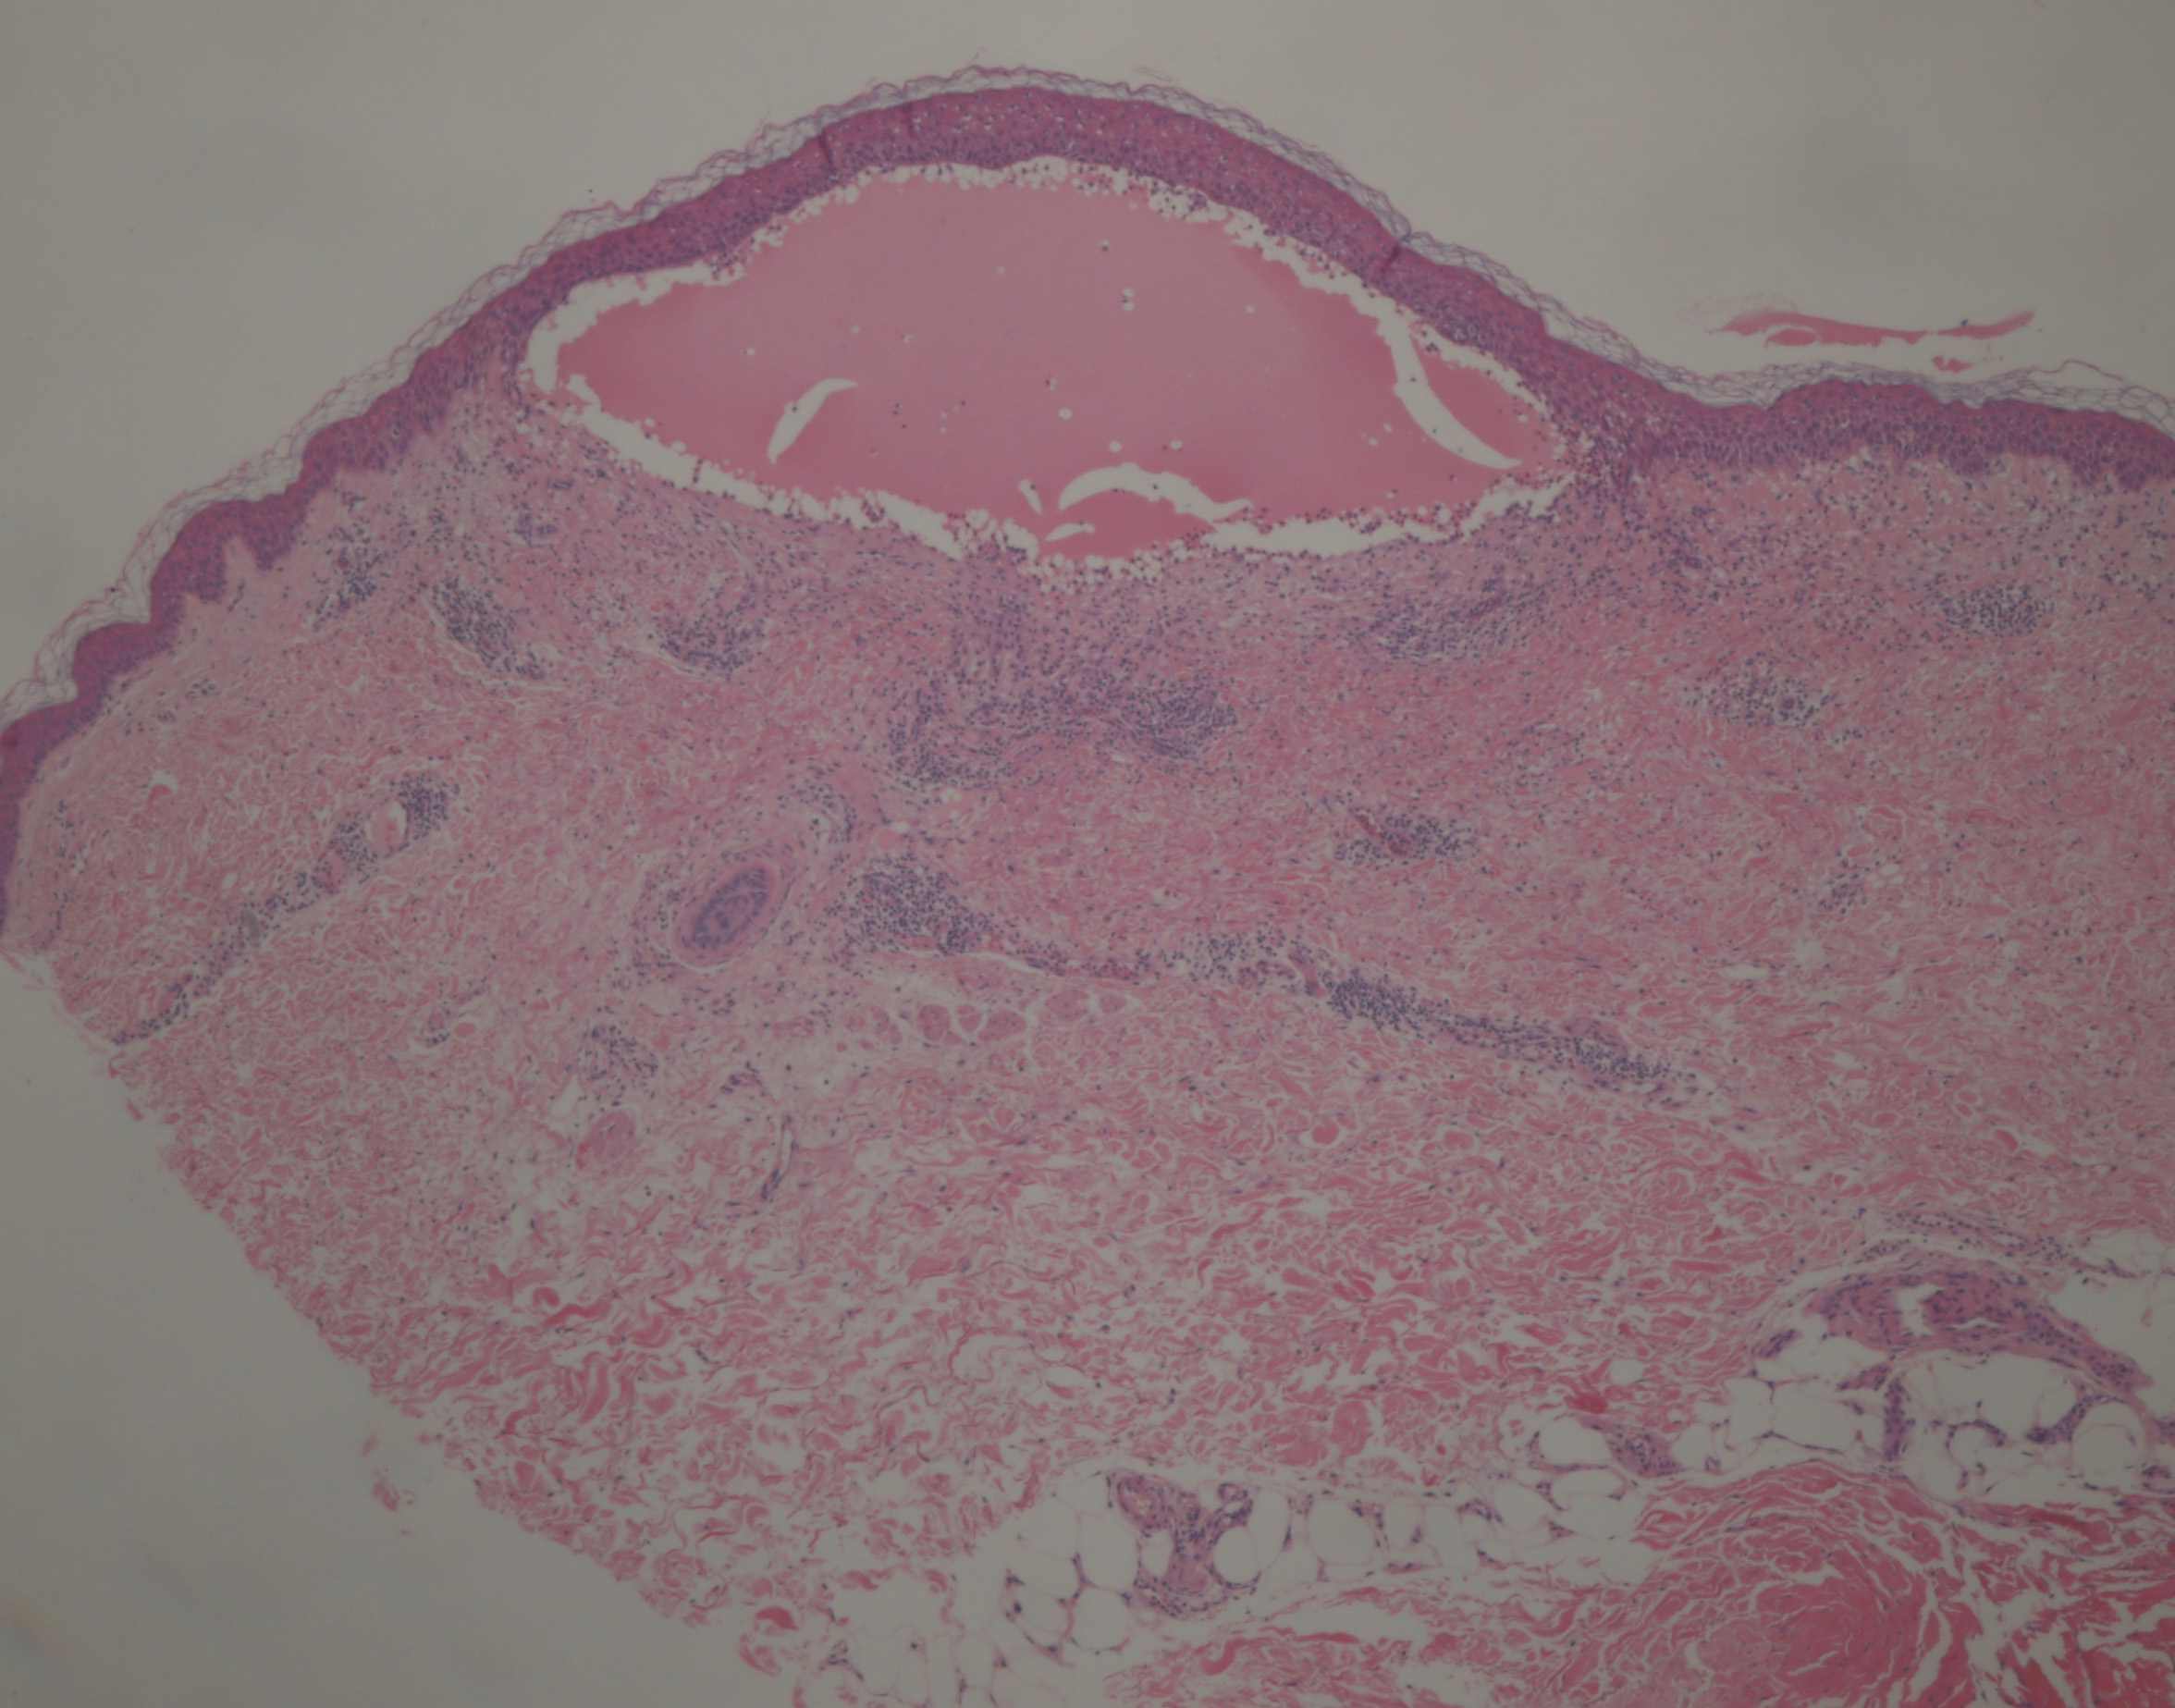

Histopathology.

In early lesions, papillary dermal edema in combination with a cell-poor or cell-rich perivascular lymphocytic and eosinophilic infiltrate is present. The blister arises at the dermal-epidermal junction . In the cell-rich pattern, which correlates clinically with blisters arising on erythematous skin , eosinophilic papillary abscesses may develop with numerous perivascular and interstitial eosinophils intermingled with lymphocytes and neutrophils in the superficial and deep dermis. Early lesions may have the histologic features of eosinophilic cellulitis (Well’s syndrome). Eosinophilic spongiosis may occur. The cell-poor pattem is observed

when blisters develop on relatively normal skin , in which there is usually a scant perivascular lymphocytic infiltrate with few eosinophils, some scattered throughout the dermis and others near the epidermis. The blister contains few inflammatory cells. Epithelial migration and regeneration may result in an intraepidermal split in older blisters. Similar to pemphigus vegetans, a hyperplasia of the epidermis, subepidermal bullae, and accumulations of eosinophils and lymphocytes may be seen.